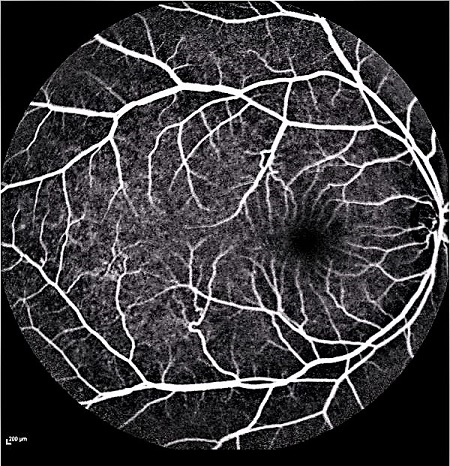

Figure 5: Three AF fundus images that are used to generate new images are seen as style images.

Furthermore, generated images from FA images are presented in Fig. 6 and Fig. 7. Results in the images are nearly identical to the original images, because original networks are applied to stylize color images. However, six generated images contain more concise features than the original ones, which helps ophthalmologists make better judgments. Therefore, this style transferring networks can fulfill edge sharpening and enhancement of contrast. No matter which kinds of images are generated, advanced features in new disease images still exist. Furthermore, analyses of image performance by EyeNet and CAMs for prediction are presented in a later section.

4.3 Style Transferring Neural Networks

Style transferring neural network in [16] was modified to generate new disease images. This network adopts layers from ”conv1 1” to ”conv4 1” in pre-trained VGG-19 [24] network for the encoder, whose weights are provided by ImageNet-pretrained weights. What’s more, multi-level stylization strategy proposed in [16] is applied to optimize the VGG features in different layers. Input images are three CFP images and three FA images as style images shown in Fig. 2 and 5. Six CFP images with three drusen and three GA images in Fig. 3 and Fig. 4. Also, FA images are applied to generate new images in Fig. 6 and Fig. 7. For CFP images, six images are shown in Fig. 3 and in Fig. 4. In Fig. 3, generated images contain round, discrete yellow-white dots, which are the symptom of drusen. In the same way, in Fig. 4, well-demarcated areas appear on the three images. Therefore, style transferring can generate new retinal symptom images.